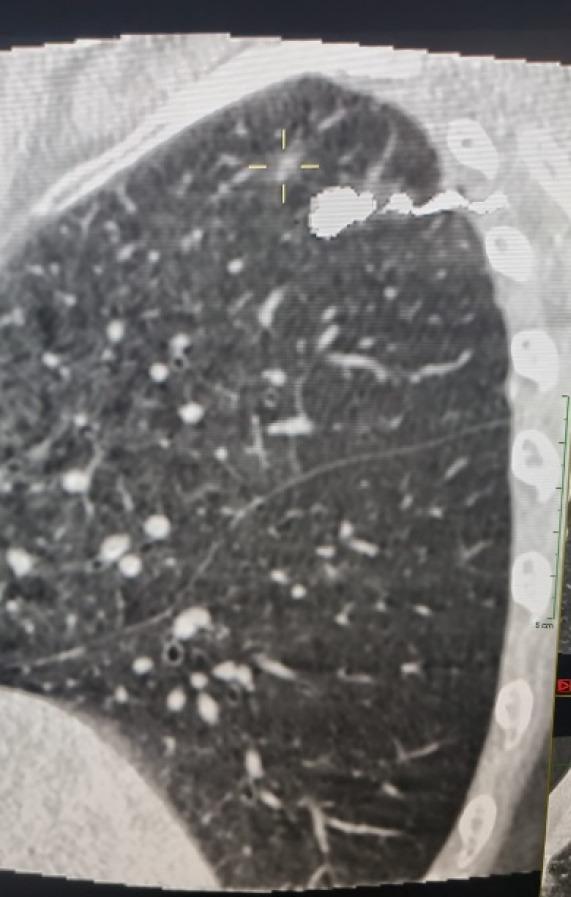

Sometimes, the identification of ground-glass opacities (GGOs), small or deep pulmonary nodules can be difficult also in expert hands. Usually for these lesions pulmonary lobectomy is an overtreatment, so we developed a technique to identify easily these nodules. The objective of this research is to assess the effectiveness and safety of using preoperative cone beam computed tomography (CBCT) to guide the placement of micro-coils in the lung parenchyma near GGO and small lesions. Additionally, the study aims to identify potential factors that could predict coil-assisted failures during uniportal video-assisted thoracic surgery (U-VATS) resections.

The clinical, radiological, and surgical records of 117 patients who underwent U-VATS resection following CBCT-guided micro-coil localization of GGOs and small deep nodules between January 2017 and February 2023 were retrospectively analyzed. We have placed a micro coil under CBCT guide before the intervention in the 24 hours preceding the intervention. The patient received a pulmonary wedge resection in U-VATS technique and an immediate fresh frozen section to determine the necessity of a pulmonary lobectomy.

有时,即使是经验丰富的医生,识别磨玻璃影(GGO)、小的或深部肺结节也可能存在困难。通常对于这些病变,肺叶切除术属于过度治疗,因此我们开发了一种能够轻松识别这些结节的技术。本研究的目的是评估术前锥形束计算机断层扫描(CBCT)引导下在GGO和小病变附近的肺实质中放置微线圈的有效性和安全性。此外,该研究旨在确定在单孔电视辅助胸腔镜手术(U-VATS)切除过程中可能预测线圈辅助失败的潜在因素。

回顾性分析了2017年1月至2023年2月期间117例在CBCT引导下对GGO和小的深部结节进行微线圈定位后接受U-VATS切除的患者的临床、放射学和手术记录。在干预前24小时内,我们在CBCT引导下放置了一个微线圈。患者接受U-VATS技术的肺楔形切除术,并立即进行新鲜冰冻切片以确定是否需要进行肺叶切除术。